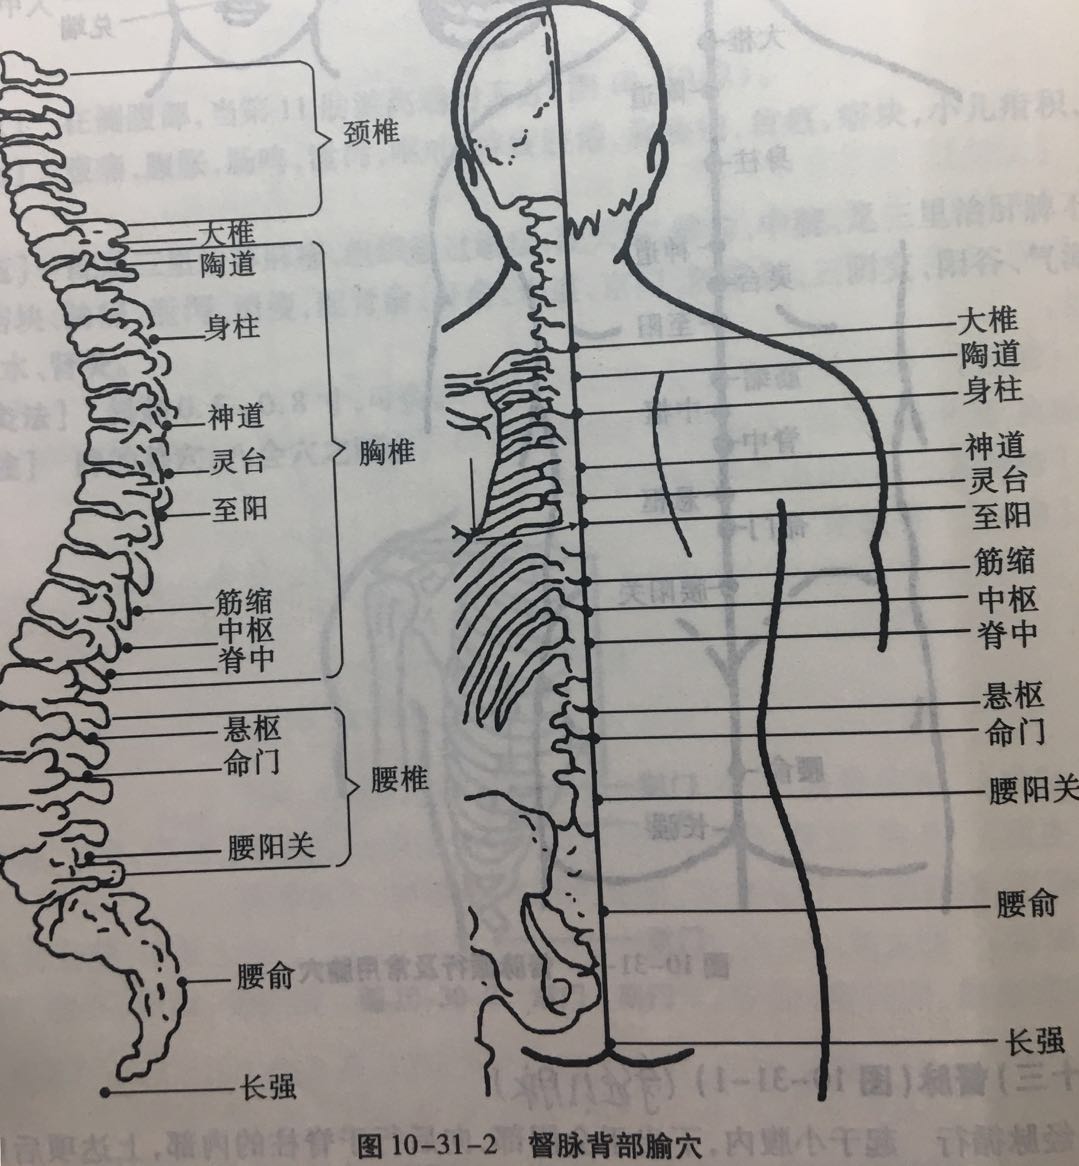

【(十三)督脉(图10-31-1)】

1、经脉循行 起于小腹内,下出于会阴部,向后行于脊柱的内部,上达项后风府,进入脑中,上行巅顶,沿前额下行鼻柱。

2、主要病候 脊柱强痛,角弓反张等证。

3、主治概要 神志疾病,热病,腰骶、背、头项、生殖疾患及循行所过部位相应内脏病证。

4、督脉歌诀 督脉行背之中行,二十八穴始长强。腰俞阳关入命门,悬枢脊中上中枢。筋缩至阳归灵台,神道身柱陶道周。大椎哑门连风府,脑户强间后顶排。百会前顶通囟会,上星神庭素髎对。水沟兑端在唇上,龈交上齿缝之内。

腰俞

【定位】 在骶部,当后正中线上,适对骶管裂孔(图 10-31-2)。

【主治】 腰脊强痛,腹泻,便秘,痔疾,脱肛,便血,癫痫,淋浊,月经不调,下肢痿痹。

【配伍】 配膀胱俞(灸)、长强、气冲、上髎、下髎、居髎治腰脊冷痛,配太冲治脊强反折、抽搐。

【刺灸法】 向上斜刺 0.5 ~ 1 寸;可灸。

腰阳关

【定位】 在腰部,当后正中线上,第 4 腰椎棘突下凹陷中(图 10-30-2)。

【主治】 腰骶疼痛,下肢痿痹,月经不调,赤白带下,遗精,阳痿,便血。

【配伍】 补腰阳关、肾俞、次髎,泻委中治腰脊痛、四肢厥冷、小便频数;配腰夹脊、秩边、承山、飞扬治坐骨神经痛、腰腿痛;配膀胱俞、三阴交治遗尿、尿频。

【刺灸法】 直刺 0.5 ~ 1 寸;可灸。

命门

【定位】 在腰部,当后正中线上,第 2 腰椎棘突下凹陷中(图 10-31-2)。

【主治】 虚损腰痛,脊强反折,遗尿,尿频,泄泻,遗精,白浊,阳痿,早泄,赤白带下,胎屡坠,五劳七伤,头晕耳鸣,癫痫,惊恐,手足逆冷。

【配伍】 配肾俞、太溪治,遗精、早泄、腰脊酸楚、足膝无力、遗尿、癃闭、水肿、头昏耳鸣等肾阳亏虚之争;配百会、筋缩、腰阳关治破伤风抽搐,灸命门、隔盐灸神阙治中风脱症;配关元、肾俞、神阙(艾灸)治五更泄,补命门、肾俞、三阴交治肾虚腰痛,泻命门、阿是穴、委中、腰夹脊穴治腰扭伤痛和肥大性脊柱炎,配十七椎、三阴交(艾灸)治痛经(寒湿凝滞型),配大肠俞、膀胱俞、阿是穴(灸)治寒湿痹腰痛。

【刺灸法】 直刺 0.5 ~ 1 寸;可灸。

中枢

【定位】 在背部,当后正中线上,第 10 胸椎棘突下凹陷中(图 10-31-2)。

【主治】 黄疸,呕吐,腹满,胃痛,食欲不振,腰背痛。

【配伍】 配命门、腰眼、阳陵泉、后溪治腰脊痛。

【刺灸法】 向上微斜刺 0.5 ~ 1 寸;可灸。

大椎

【定位】 在后正中线上,第 7 颈椎棘突下凹陷中(图 10-31-2)。

【主治】 热病,疟疾,咳嗽,喘逆,骨蒸潮热,项强,肩背痛,腰脊强,角弓反张,小儿惊风,癫狂痫证,五劳虚损,七伤乏力,中暑,霍乱,呕吐,黄疸,风疹。

【配伍】 配肺俞治虚损、盗汗、劳热,配间使、乳根治脾虚发疟,配四花穴治百日咳(双膈俞、双胆俞),配曲池预防流脑,配合谷治白细胞减少,配足三里、命门提高机体免疫力,配大椎、定喘、孔最治哮喘,配曲池、合谷泻热,配腰奇、间使治癫痫。

【刺灸法】 斜刺 0.5 ~ 1 寸;可灸。